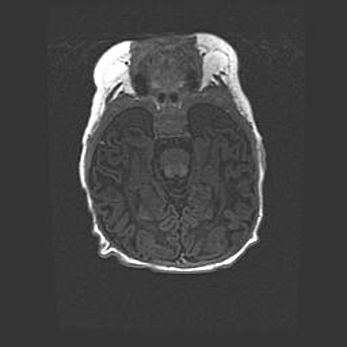

Наружная гидроцефалия с возможной атрофией височных областей.

Возраст: 28 дней

Вес: 3670 г

Пол: мужской

Окружность головы: 38 см

Срок гестации: 40 недель

Гидроцефалия головного мозга у новорожденных – это заболевание, которое характеризуется скоплением избыточного количества спинномозговой жидкости в желудочковой системе головного мозга в результате затруднения её перемещения от места выработки к месту поглощения в кровеносную систему или вследствие нарушения абсорбции. При открытой наружной форме гидроцефалии у новорожденных расширяются и переполняются субарахноидные пространства.

При нормотензивных  формах,  которые,  как  правило,  являются  следствием  перенесенных ишемических  повреждений  паренхимы  мозга,  возможно  сочетание микроцефалии  с нормотензивной гидроцефалией. В основе данных изменений лежит атрофия больших полушарий с преимущественной  локализацией  в  лобно-височных  областях.